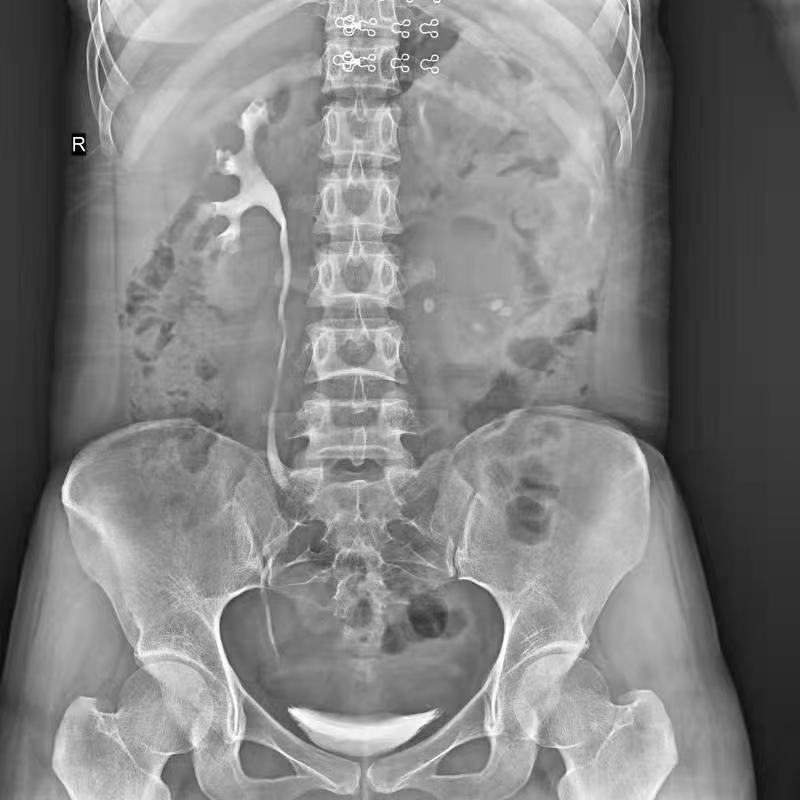

全自動(dòng)拼接

●呈現(xiàn)全下肢或全脊柱圖像

●在脊柱及下肢畸形矯正手術(shù)治療中,為術(shù)前方案制定和術(shù)后復(fù)查提供精準(zhǔn)測(cè)量

●有效解決傳統(tǒng)X光片不能一次成像問題,為患者提供更加優(yōu)質(zhì)的醫(yī)療服務(wù)

Clinical picture

臨床圖片